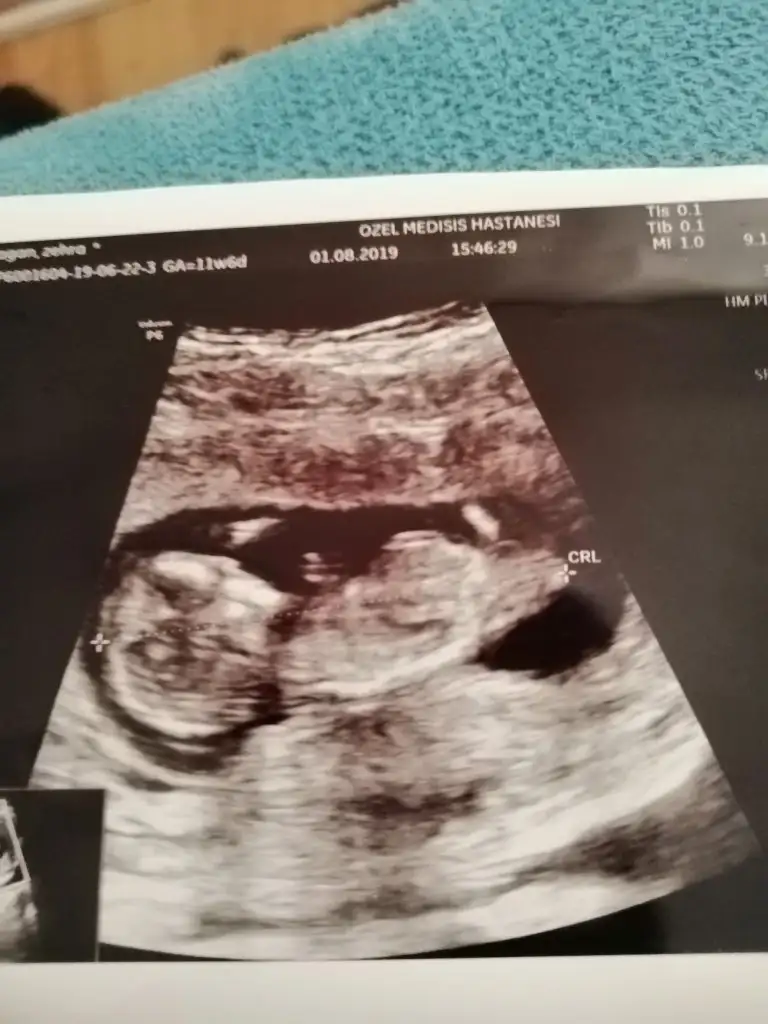

Kızlaar benim bebişede bi yorum yapsanız bende merak ediyorum cinsiyeti

Eki Görüntüle 2294674

Eki Görüntüle 2294675

Eki Görüntüle 2294676